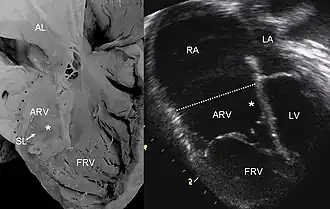

![]() УЗИ изображение патологического состояние сердца при Аномалии Эбштейна. | |

Эхокардиографическое исследование. Отмечаются деформация эхосигнала от створок и объемное увеличение размеров правого предсердия.